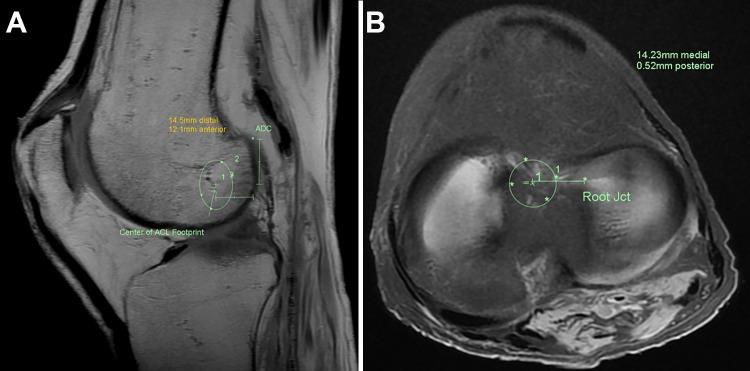

On the tibial side, the median distance between the center of the native and reconstructed ACL footprints in relation to the root of the anterior horn of the lateral meniscus medially was 1.7 ± 2.2 mm and 1.9 ± 2.8 mm for the standard and roadmapped techniques, respectively ( = .442), while the median anteroposterior distance was 3.4 ± 2.4 mm and 2.5 ± 2.5 mm for the standard and roadmapped techniques, respectively ( = .161). On the femoral side, the median distance in relation to the apex of the deep cartilage (ADC) distally was 0.9 ± 2.8 mm and 1.3 ± 2.1 mm for the standard and roadmapped techniques, respectively ( = .195), while the median distance anteriorly from the ADC was 1.2 ± 1.3 mm and 4.6 ± 4.5 mm for the standard and roadmapped techniques, respectively ( = .007).

在胫骨侧,标准技术和路线图技术中,天然与重建前交叉韧带足迹中心相对于内侧半月板前角根部的中位数距离分别为1.7±2.2 mm和1.9±2.8 mm(P = 0.442),而标准技术和路线图技术的前后中位数距离分别为3.4±2.4 mm和2.5±2.5 mm(P = 0.161)。在股骨侧,标准技术和路线图技术中,相对于远端深层软骨顶点(ADC)的中位数距离分别为0.9±2.8 mm和1.3±2.1 mm(P = 0.195),而标准技术和路线图技术中,从ADC向前的中位数距离分别为1.2±1.3 mm和4.​​6±4.5 mm(P = 0.007)。